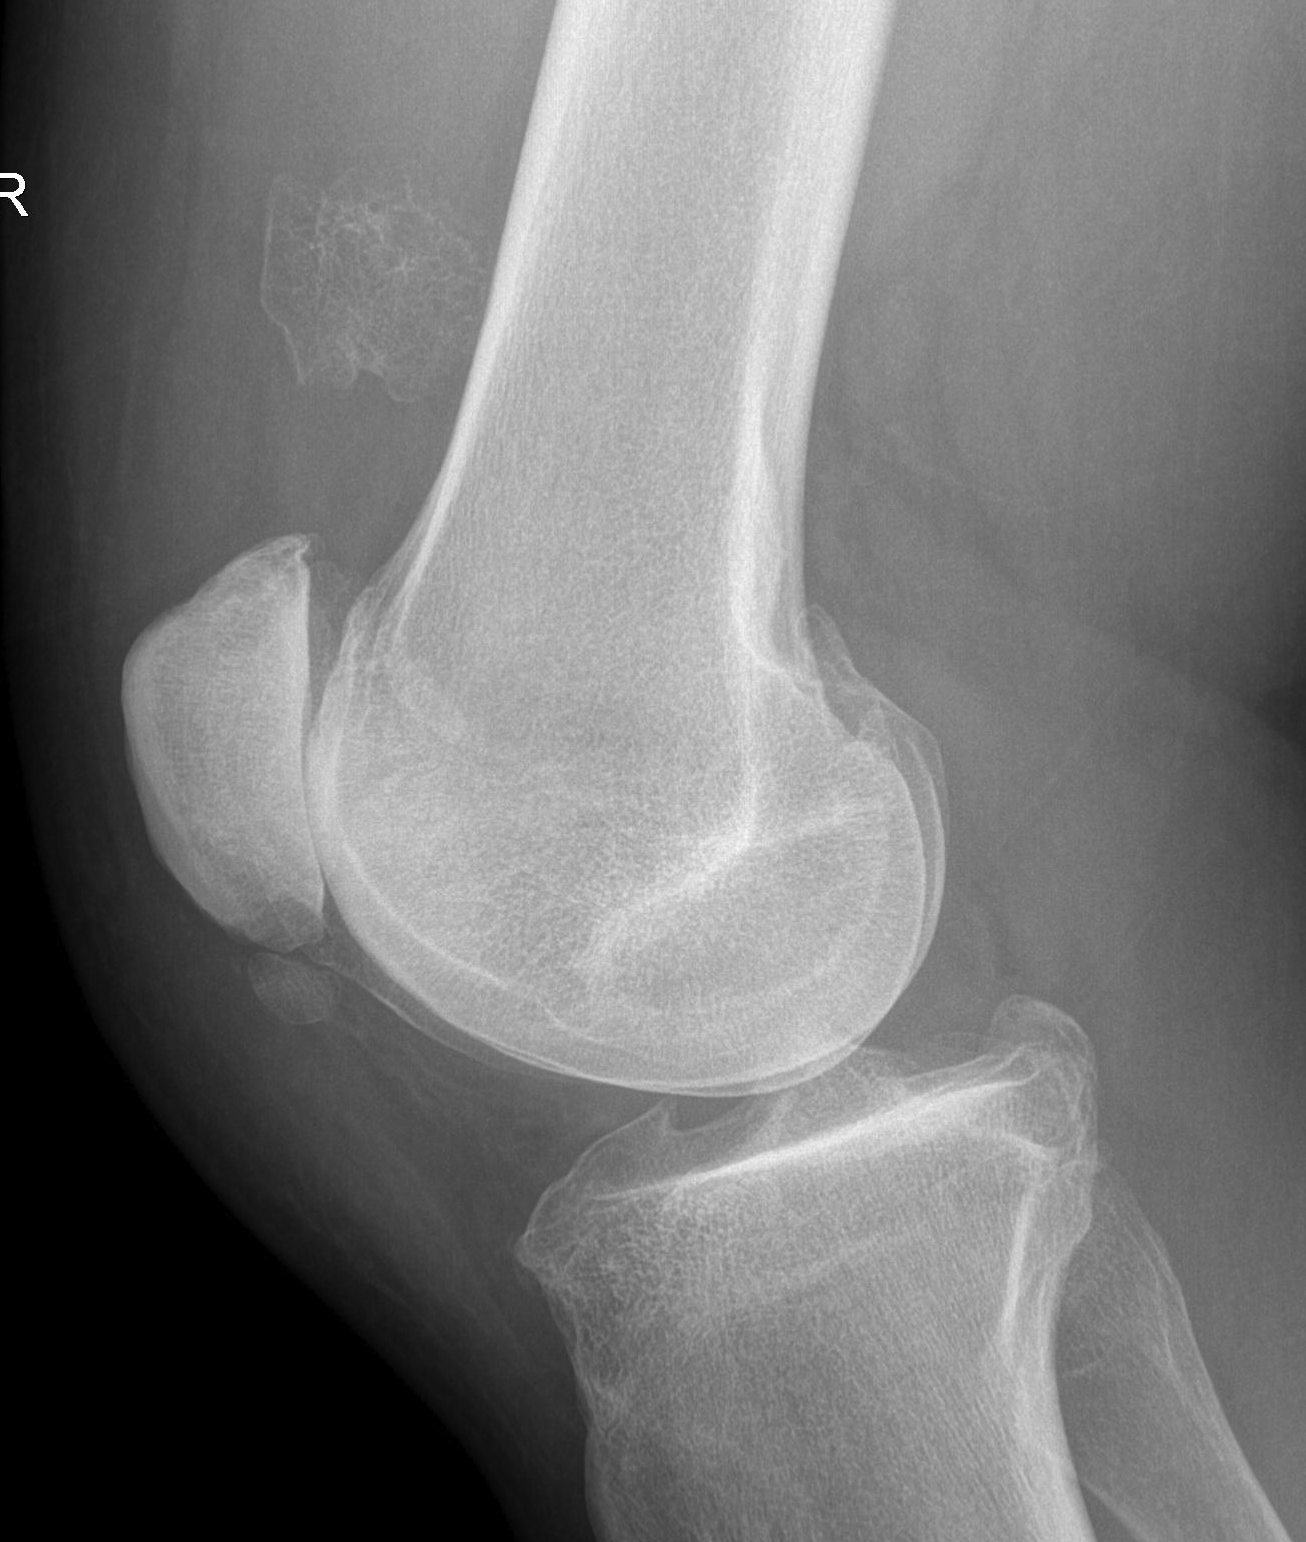

X-ray

May look like osteochondroma

- large lobulated broad-based lesion

- mature bone arising from cortex

- underlying cortex may be thickened

- 25% invade periosteum

"String Sign"

- wraps around bone with intervening periosteum

- well-defined radiolucent line between lesion & cortex

Parosteal osteosarcoma distal femur